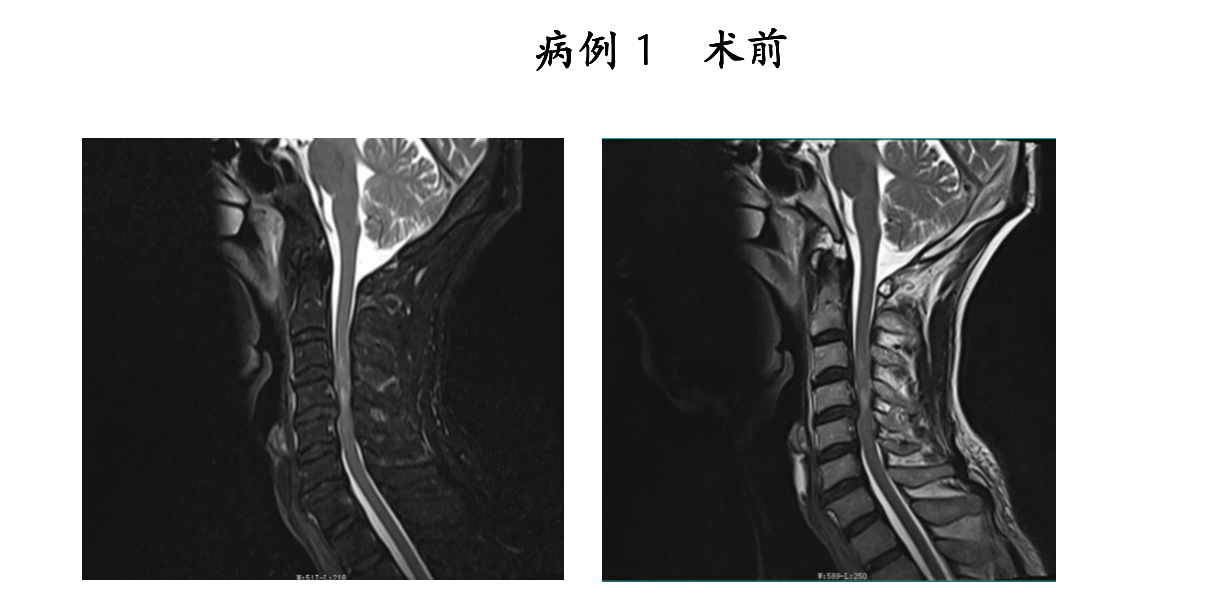

大众卫生报·新湖南客户端3月9日讯(通讯员 匡登峰 申宽宏)近日,祁东县人民医院脊柱外科团队再传捷报。在衡阳市中心医院派驻专家申宽宏副主任医师的带领下,团队成功为2名颈脊髓损伤患者实施了“内镜辅助下颈椎前路减压融合内固定术”。术后患者神经功能恢复良好,疼痛症状显著缓解,康复进程远超预期,赢得了患者及家属的高度赞誉。

颈脊髓损伤是脊柱外科领域的急危重症。由于病变部位毗邻重要的神经和血管,手术操作空间狭小,对精准度的要求极高。传统开放手术虽然有效,但存在创伤大、术后恢复慢等问题,对医生的技术和经验是极大的考验。

高清内镜下“精准拆弹”,实现脊髓“零侵袭”

手术过程中,团队仅通过微小切口建立内镜通道,直达脊柱病变部位。在高清内镜的实时视野下,脊髓、神经根及周围血管等组织结构清晰可见,真正实现了可视化操作。

医疗团队在镜下精准完成了椎间盘/髓核摘除、椎管减压等核心步骤,彻底解除了脊髓与神经的压迫。随后,通过微小切口精准植入融合器与内固定装置,有效重建了脊柱的生理曲度与力学平衡。

相较于传统开放手术,该术式具有创伤小、出血少、疼痛轻、恢复快的显著优势。术中实现了对脊髓的“零侵袭”,极大降低了手术风险,为患者的快速康复奠定了坚实基础。